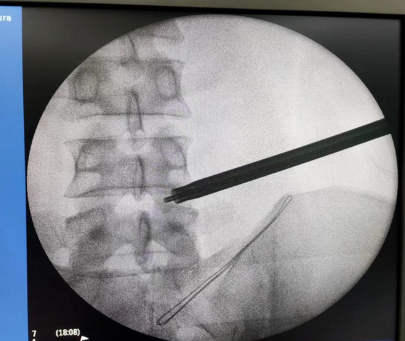

手术经过:术前仔细阅片,精确定位手术靶点部位、规划手术路径、测量通道长度、头尾倾角度。C臂透视定位、局部麻醉、穿刺建立通道、环锯进行关节突成形,连接椎间孔镜系统、椎间盘摘除、神经根管探查减压、侧隐窝减压、彻底检查无卡压后关闭伤口。手术成功,患者术后3天康复出院。

术前定位及切口

术中穿刺及关节突成形